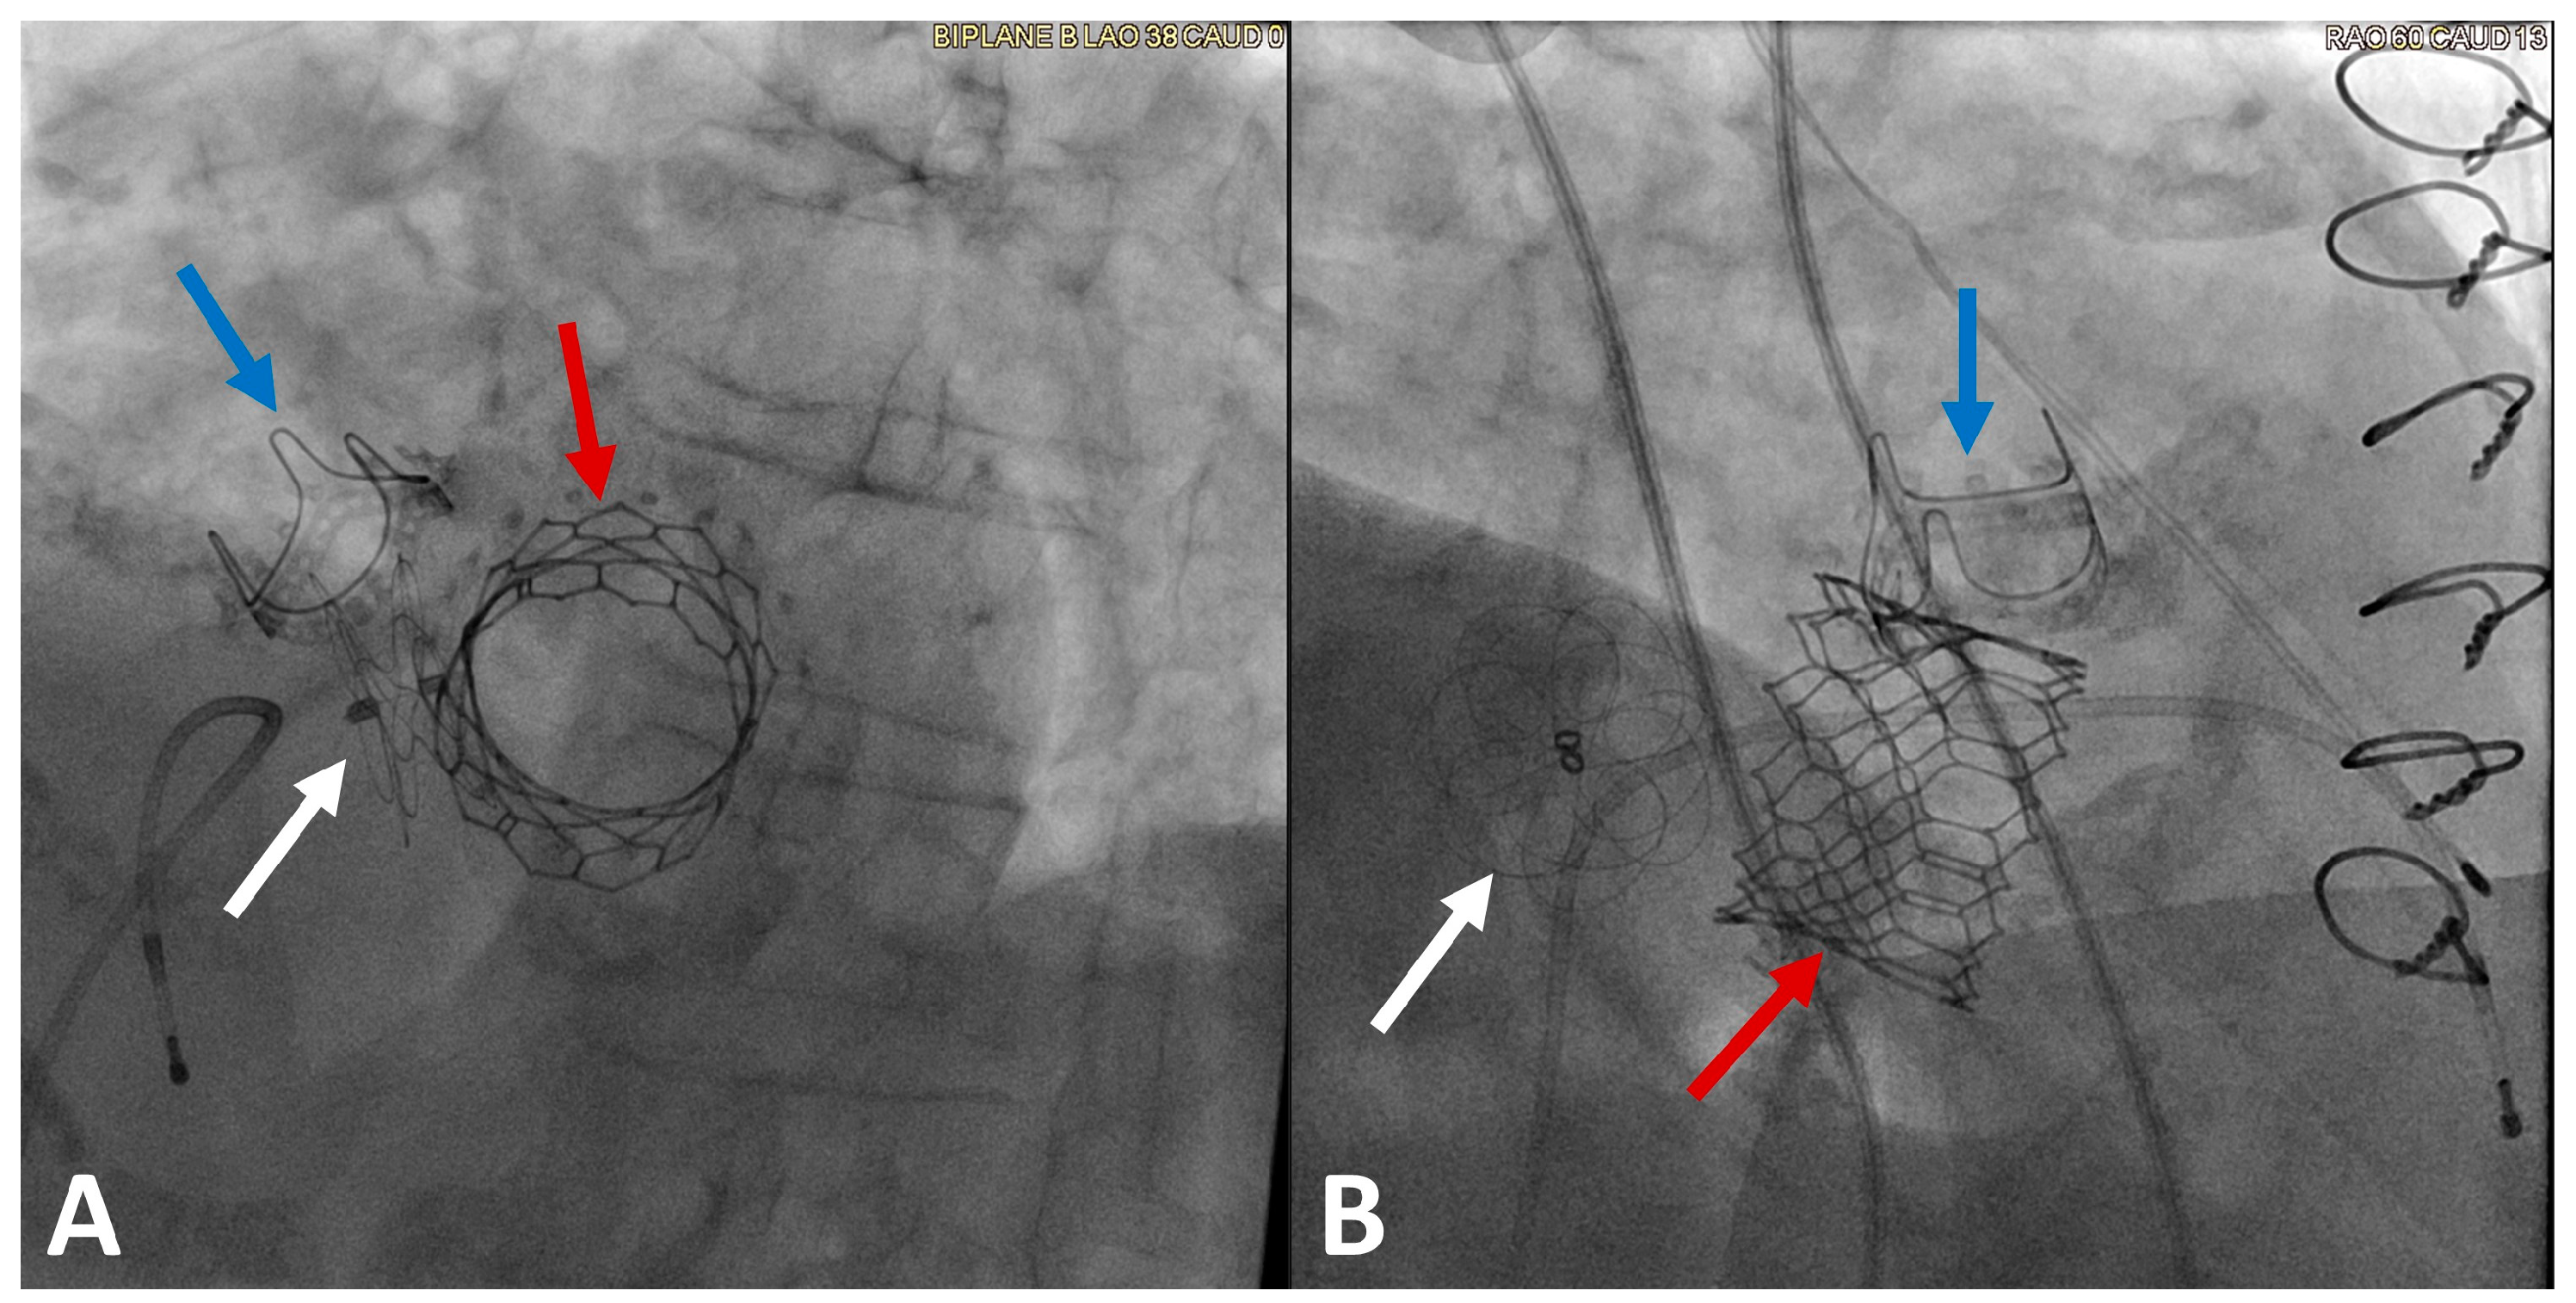

5. Mitral Paravalvular Leak Closure

- Cruz-Gonzalez, I.; Rama-Merchan, J.C.; Rodríguez-Collado, J.; Martín-Moreiras, J.; Diego-Nieto, A.; Barreiro-Pérez, M.; Sánchez, P.L. Transcatheter closure of paravalvular leaks: State of the art. Neth. Heart J. Mon. J. Neth. Soc. Cardiol. Neth. Heart Found. 2017, 25, 116–124. [Google Scholar] [CrossRef]

- Gafoor, S.; Franke, J.; Bertog, S.; Lam, S.; Vaskelyte, L.; Hofmann, I.; Sievert, H.; Matic, P. A Quick Guide to Paravalvular Leak Closure. Interv. Cardiol. 2015, 10, 112–117. [Google Scholar]

- Gafoor, S.; Steinberg, D.H.; Franke, J.; Bertog, S.; Vaskelyte, L.; Hofmann, I.; Sievert, H. Tools and Techniques—Clinical: Paravalvular leak closure. Eurointervention J. EuroPCR Collab. Work. Group Interv. Cardiol. Eur. Soc. Cardiol. 2014, 9, 1359–1363. [Google Scholar] [CrossRef] [PubMed]

- García, E.; Sandoval, J.; Unzue, L.; Hernandez-Antolin, R.; Almeria, C.; Macaya, C. Paravalvular leaks: Mechanisms, diagnosis and management. Eurointervention J. EuroPCR Collab. Work. Group Interv. Cardiol. Eur. Soc. Cardiol. 2012, 8, Q41–Q52. [Google Scholar] [CrossRef]